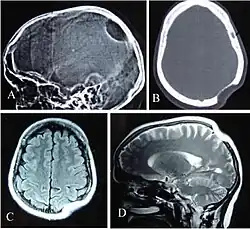

Rundlicher Knochendefekt der Schädelkalotte bei Gorham-Stout-Syndrom. Oben Röntgen und Computertomographie, unten Magnetresonanztomographie.